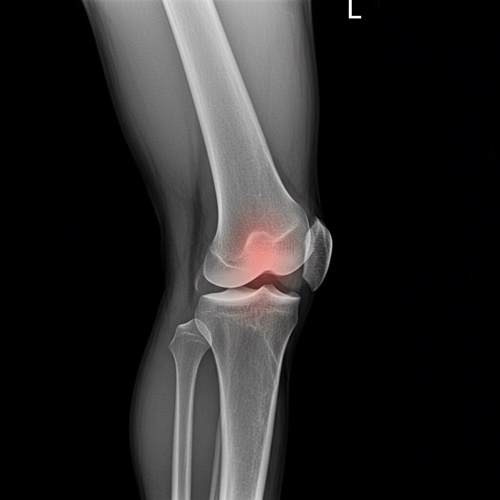

1기는 자각 증상이 거의 없거나 간헐적인 불편함 정도로, 무릎에 약간의 뻣뻣함이 느껴지고 운동 후에만 통증이 있는 경우가 많아요. 이 시기는 엑스레이 검사에서도 큰 이상이 나타나지 않을 수 있어요. 반면, 2기에는 통증이 점점 자주 발생하고, 무릎을 꺾거나 움직일 때 소리가 나거나 저림 증상까지 동반될 수 있어요. 이 단계부터는 엑스레이 상에서 연골의 마모와 관절 간격 감소가 관찰돼요. 무릎 관절염 증상을 이 시점에서 인지하고 적절한 조치를 취하는 것이, 이후 진행을 막는 중요한 전환점이 돼요.

무릎 관절염은 보통 4단계로 구분돼요. 1기는 통증이 거의 없거나 일시적인 수준이고, 2기에는 일상생활 중 통증과 뻣뻣함이 발생해요. 3기부터는 연골 손상이 명확해지고, 4기는 연골이 거의 닳아 관절 간격이 사라지며 극심한 통증과 기능 저하가 나타나요. 무릎 관절염 증상이 반복되고 악화된다면 빠른 진단과 대처가 필요해요.